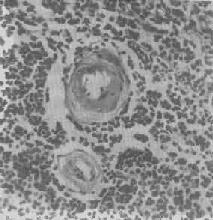

图1-18 肝细胞脂肪变性 肝细胞胞浆内出现大小不等的脂肪空泡;右上角为饿酸染色的脂肪细胞, 脂滴染成黑色 (2)心肌脂肪变性:心肌在正常情况下可含有少数脂滴,脂肪变性时脂滴明显增多。镜下,脂肪空泡较细小,呈串珠状成排排列,主要位于肌纤维Z带附近和线粒体分布区。常为贫血和中毒的结果。在严重贫血时,可见心膜下尤其是乳头肌处出现成排的黄色条纹,与正常心肌的暗红色相间排列,状若虎皮斑纹,故有“虎斑心”之称。严重感染、白喉外毒素以及其他毒物(如磷、砷、氯仿等)也能引起心肌的弥漫性脂肪变。肉眼观,心肌均匀变浊,略呈黄白色。但通常心功能并不受明显影响。显著的心肌脂肪变性如今并不常见。 (3)肾脂肪变性;在严重贫血、缺氧和中毒过程中,或肾小球毛细血管通透性升高时,肾小管特别是近曲小管的上皮细胞可吸收漏出的脂蛋白而导致脂肪变性。脂滴起初多位于细胞基底部。肉眼观,肾稍肿大,切面上可见皮质增厚,略呈浅黄色。 2.玻璃样变性 又称透明变性(hyaline degeneration),为十分常见的变性,主要见于结缔组织、血管壁,有时也可见于细胞内。 1.结缔组织玻璃样变:常见于纤维瘢痕组织、纤维化的肾小球,以及动脉粥样硬化的纤维性瘢块等。此时纤维细胞明显变少,胶原纤维增粗并互相融合成为梁状、带状或片状的半透明均质,失去纤维性结构(图1-19)。质地坚韧,缺乏弹性。玻璃样变的发生机制尚不甚清楚,有人认为在纤维瘢痕老化过程中,原胶原蛋白分子的交联增多,胶原原纤维也互相融合,其间并有较多的糖蛋白积聚,形成所谓玻璃样物质;也有人认为可能由于缺氧、炎症等原因,造成局部pH升高或温度升高,致使原胶原蛋白分子变性成明胶并互相融合所致。 2.血管壁玻璃样变:这种改变常见于高血压病时的肾、脑、脾及视网膜的细动脉。此时,可能是由于细动脉的持续性痉挛,使内膜通透性增高,血浆蛋白得以渗入内膜,在内皮细胞下凝固成无结构的均匀红染物质。此外,内膜下的基底膜样物质增多。这些改变使细动脉的管壁增厚、变硬,管腔变狭,甚至闭塞(图1-20),此即细动脉硬化症(arteri-olosclerosis),可引起肾及脑的缺血。 3.细胞内玻璃样变:亦称为细胞内玻璃样小滴变性。这种情况常见于肾小球肾炎或其他疾病而伴有明显蛋白尿时。此时肾近曲小管上皮细胞胞浆内可出现许多大小不等的圆形红染小滴(图1-21),这是血浆蛋白经肾小球滤出而又被肾小管上皮细胞吞饮的结果,并在胞浆内融合成玻璃样小滴,以后可被溶酶体所消化。此外,在酒精中毒时,肝细胞核周胞浆内亦可出现不甚规则的红染玻璃样物质。电镜下,这种物质由密集的细丝构成,据认为可能是细胞骨架中含角蛋白成分改变的结果,并被称为Mallory小体。

图1-20 脾中央动脉玻璃样变 中央动脉管壁明显增厚,呈玻璃样均质状,管腔变窄 4.粘液性变性 组织间质内出现类粘液的积聚称为粘液样变性(mucoid degeneration)。镜下可见病变处的间质变疏松,充以染成淡蓝色的胶状液体,其中有一些多角形、星芒状细胞散在,并以突起互相联缀。 结缔组织粘液样变性常见于间叶性肿瘤、急性风湿病时的心血管壁、动脉粥样硬化的血管壁。甲状腺功能低下时,全身皮肤的真皮及皮下组织的基质中有较多类粘液(mucoid)及水分潴留,形成粘液水肿(myxedema),其机制可能是甲状腺功能低下时,能促进透明质酸酶活性的甲状腺素分泌减少,致透明质酸(类粘液的主要成分之一)降解减弱而大量潴积于组织内。 粘液样变性当病因消除后可以逐渐消退,但如长期存在,则可引起纤维组织增生,从而导致组织硬化。 5.淀粉样变性 组织内有淀粉样物质沉积称为淀粉样变性(amyloid degeneration,amyloidosis)。淀粉样物质为一种结合粘多糖的蛋白质,遇碘时被染成赤褐色,再加以硫酸则呈蓝色,与淀粉遇碘时的反应相似,故称之为淀粉样物质。此物质常浸润于细胞间或沉积于小血管的基底膜下,或沿网状纤维支架分布(图1-22)。淀粉样物质在HE染色切片中为淡红色均质状,电镜下则为纤细的丝状。